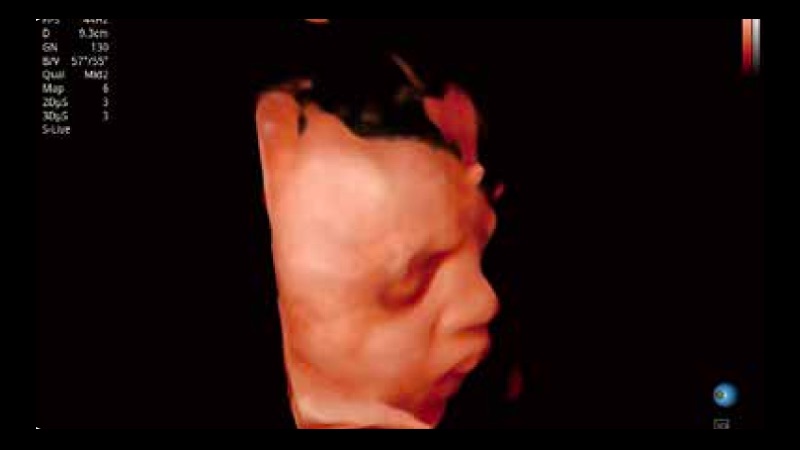

凭借狗万官方网站先进的成像技术和优异的探头技术提供的清晰的图像表现,您可以更自信地做出临床决策。